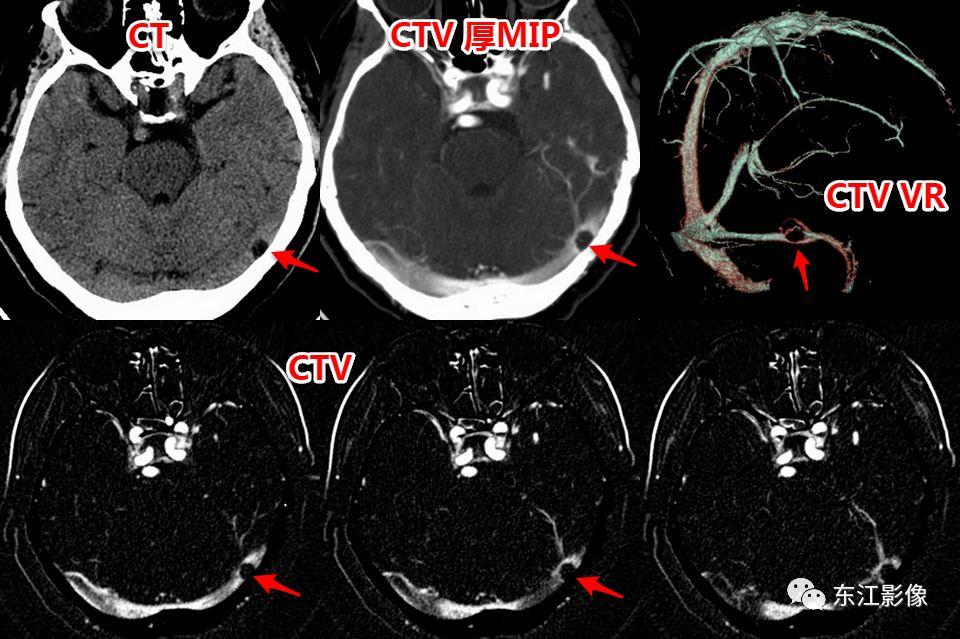

2. 静脉窦内扩大的蛛网膜颗粒

- 蛛网膜在硬脑膜构成的静脉窦附近形成许多绒毛状突起,突入静脉窦内,形成静脉窦内蛛网膜颗粒。

- 随着头颅MRI的广泛使用,静脉窦内扩大的蛛网膜颗粒“变得”非常常见。

- 不熟悉的话,容易误诊为异常。

- 以横窦常见(横断面图像最容易被发现的缘故),其次为上矢状窦,直窦、乙状窦少见,海绵窦罕见。

- CT平扫,呈稍高密度背景内低密度充盈缺损。

- MRI T1WI为低信号,稍高于脑脊液信号;T2WI为高信号,FLAIR多为低信号,稍高于脑脊液信号,较大的其内可见絮状稍高信号;增强多无强化,较大的其内可见点、线状强化灶。MRV上均呈附壁状充盈缺损。

- 极少数静脉窦内扩大的蛛网膜颗粒可能会引起静脉窦狭窄,DSA实时压力测量是确诊工具。

右侧横窦扩大的蛛网膜颗粒。

左侧横窦扩大的蛛网膜颗粒。